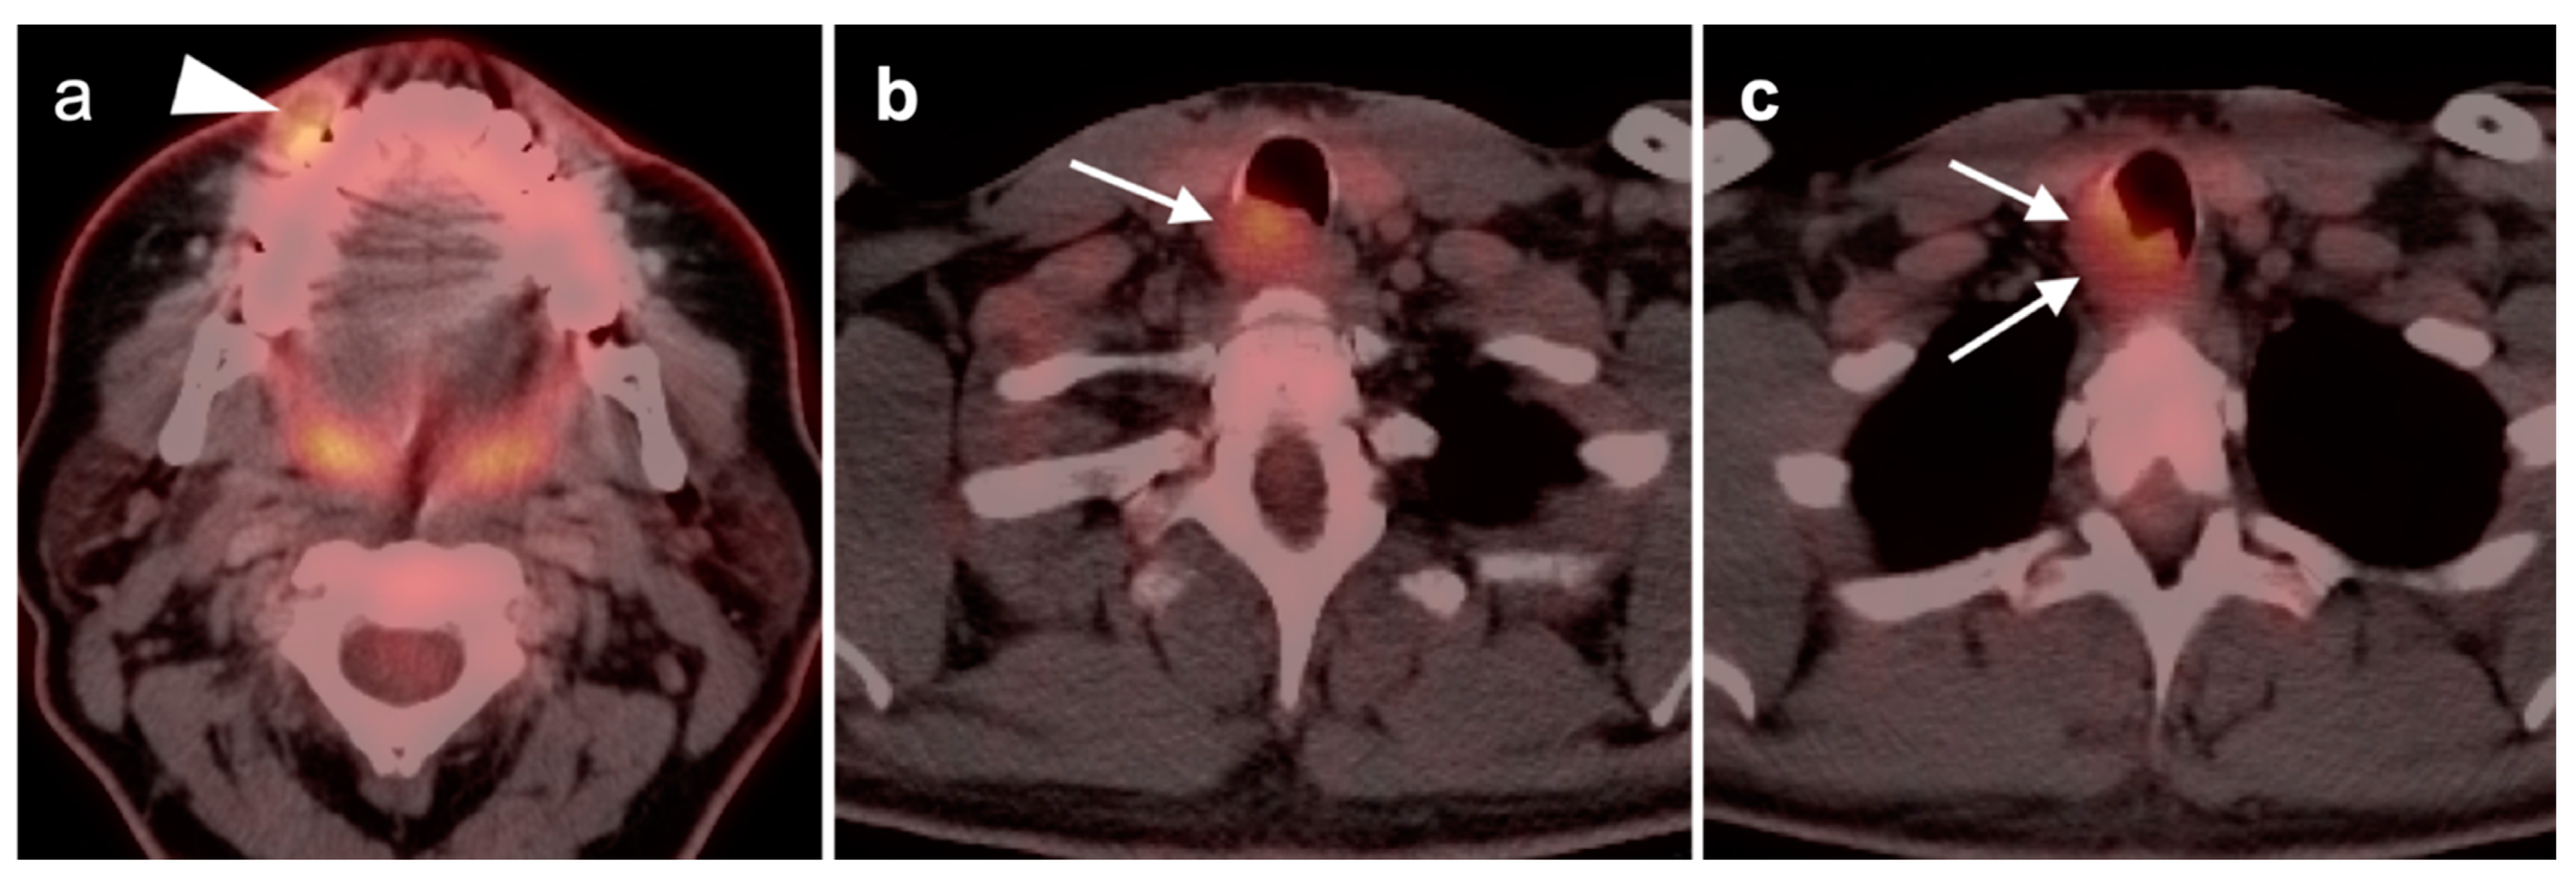

2.6. Thyroid Cancer

- Differentiated thyroid cancer

- Anaplastic thyroid cancer

- Medullary thyroid cancer